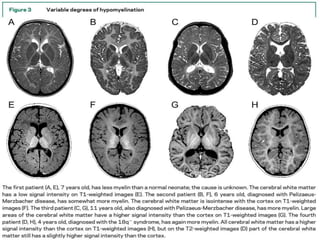

De-myelination Vs hypo-myelination

Demyelination:

• Prominent T2 hyperintensity.

• Prominent T1 hypointensity.

Hypomyelination:

• Mild T2 hyperintensity.

• Variable T1 signal (hypo, iso or hyperintense).